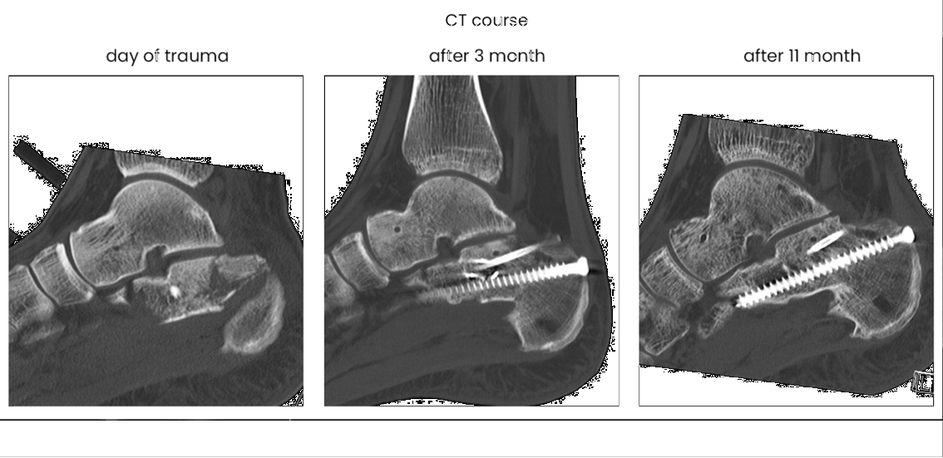

case 17BD, 47 years old, male, fall during work, 2 meters, "comminuted fracture", surgery after 2 days